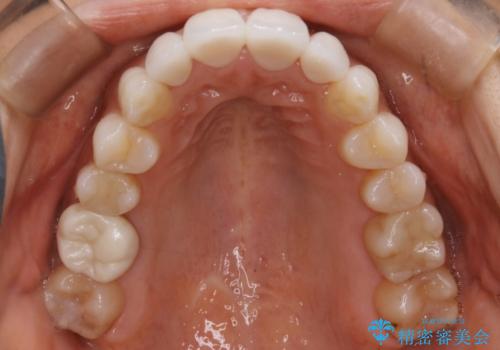

- 嚙み合わせのズレを主訴にご来院されました。

前歯・奥歯ともにセラミッククラウンで治療されている歯があったため、その歯にあまり影響が出ない範囲内で全体の噛み合わせが良くなるような動きを組み込んで治療を進めることとなりました。

矯正治療前にセラミック等の被せ物をされている場合、それ自体の外形は矯正治療では変更することができないため、その他の天然歯の移動に影響を与えてしまう場合があります。また、治療上設定されるアタッチメント(歯の表面に付けるプラスチックの突起)が付かない場合が多く、歯のコントロールが不足する場合があります。